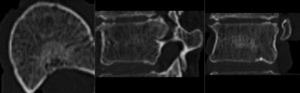

Registration Results

RegLib C39 unregistered.gif before registration (click to enlarge)

RegLib C39 registered.gif after rigid alignment. (click to enlarge)

8. use fade slider to verify alignment; compare with result snapshots shown below.

9. note: you can also change the colormaps for the fixed and moving volumes to better judge the alignment: go to the Volumes module and in the Display tab, select "green" and "magenta" as the respective colormaps for the two volumes.